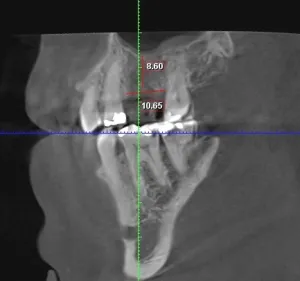

It amazes us how well people can heal sometimes. This case, done by Dr. Wes Parker, involved a 45 year old male who was referred for a carious, necrotic (dead) tooth #14 (upper left first molar). The patient also reported left sided sinus pressure and drainage. At his consultation, we obtained a Cone Beam CT (CBCT) scan. On his CBCT, you could see where the infection and inflammation from tooth #14 had eroded through the floor of the left maxillary sinus. We discussed this with him and scheduled surgery shortly after the consultation. Dr. Parker removed tooth #14, cleaned out the pus and inflamed maxillary sinus lining through the socket. The inflamed, thickened sinus lining went almost up to the orbit (eye socket). Dr. Parker then closed off the sinus communication. Following this, Dr. Parker placed a bone graft over the sinus closure, and then sutured over that to close the wound. The patient healed very well. He was compliant with the sinus precautions and medications that were prescribed. Next, Dr. Parker proceeded with implant placement in the #14 site with a simultaneous indirect sinus lift or “sinus bump.” The implant placement surgery went well, and after about 5 months of healing time, the patient received a crown on the implant from his dentist. Image #1 is a preoperative PA radiograph of the carious, necrotic, nonrestorable tooth #14 (upper left first molar). Image #2 is a coronal slice from the patient’s preoperative CBCT showing the necrotic tooth #14 with a periapical radiolucency and maxillary sinus inflammation stemming from the necrotic tooth. Image #3 is a sagittal slice from the patient’s preoperative CBCT showing the necrotic tooth #14 with a periapical radiolucency and maxillary sinus inflammation stemming from the necrotic tooth. Image #4 is a sagittal CBCT slice from the patient’s post extraction CBCT showing resolution of the sinus inflammation and measurements for the future dental implant. Image #5 is an immediate postoperative PA of the implant in the #14 site following implant placement with a simultaneous indirect sinus lift. Image #6 is a 5 month postoperative PA showing the healed, integrated implant prior to crown placement with a healed sinus lift bone graft above it and no sinus inflammation.